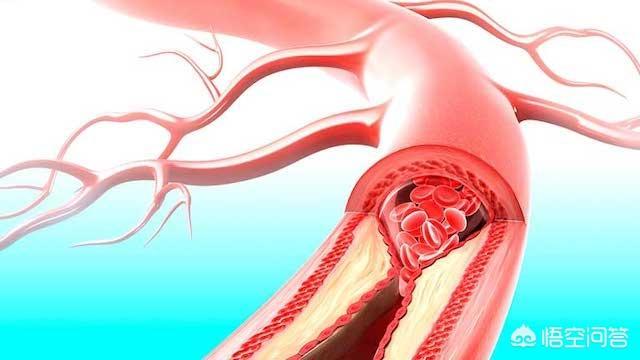

そして、アテローム性動脈硬化プラークは一般的な慢性病変であり、その発生と発症は高血圧、糖尿病、高脂血症などの多くの要因に影響される。長期にわたる高血圧、高血糖、高脂血症を管理しないと、人体各部の動脈に動脈硬化性プラークが発生しやすくなり、この動脈硬化性プラークが脳動脈に発生すると、脳血栓症発生の下地を作ることになる。たとえば、時間の経過とともに、血圧、血糖、血中脂質がまだコントロールされていない、アテローム性プラークがますます大きくなり、ますます不安定になり、この時、アテローム性プラークが大きくなりすぎたり、突然破裂したりすると、その場で血栓症が発生し、動脈血管が閉塞し、脳梗塞も発生する。

人体を例にとって言えば、水道管の老化は動脈硬化のようなもので、動脈硬化がプラークを生成するのは「さび色の斑点」、「汚れ」のようなものだ。

違いは、プラークが破裂して血栓症を促進する可能性があることで、これが心血管疾患の急性発作の原因である。

実際、血栓症は防御機構である:

例えば、皮膚が破れて出血した場合、出血は自動的に止まるが、これは血栓症の結果である。 血栓が形成され、破れを塞ぐことで出血が止まるのである。しかし、この破断は血管のプラーク上で起こり、破断した場所から自ら修復して血栓が形成されるが、血管局所では限られたスペースしかないため、血管の局所的な狭窄、あるいは閉塞を引き起こす。

頸動脈は、重度のプラーク、つまり不安定プラークが発生すると、一度破裂したプラークが血栓を形成し、この血栓が脳血管に流れて脳血管を閉塞し、脳梗塞を引き起こす。

頸動脈プラークが形成される主な理由は動脈硬化であり、動脈硬化が形成される主な理由は、不健康な食事、喫煙と飲酒、肥満、運動不足の座りっぱなし、プレッシャーの多い徹夜、コントロールできない三高、遺伝的理由などである。特に不健康な生活と三高に注意しないと、動脈硬化が加速する。だから、動脈硬化の予防は、子供の頃から健康的な生活習慣を身につけることである。